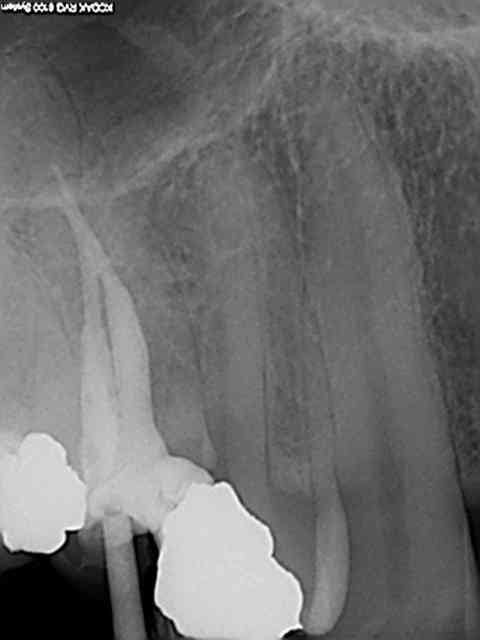

logement canalaire au largo 3, puis machtou vert chauffé au chalumeau.

Radio cône en place avant de le sceller, avec un bon tuck- back et le machtou chauffé au rouge il est rare que le cône reste collé au fouloir. L'avantage de faire la provisoire dans la séance permet de descendre la couronne en plateau et de bien visualiser la chambre pulpaire, particulièrement indiqué dans le cas ci dessus sur des 31 41 d'une personne âgée pulpe rétractée ou à force de la chercher tu trouves .... le desmodonte !))))).